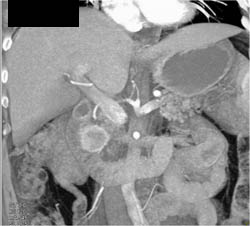

Calcified Node Near Pancreas